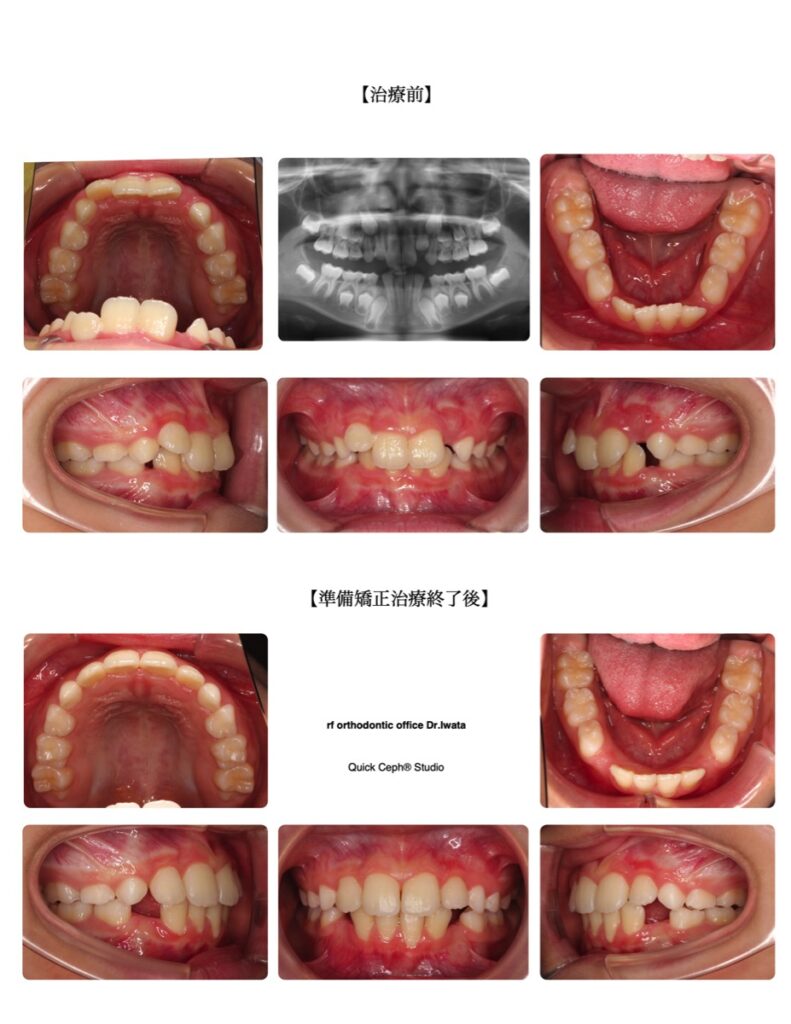

過蓋咬合症例 <叢生を伴う過蓋咬合に対する準備矯正治療>

【主訴】かみ合わせが深く、上の前歯が変な向きで生えてきた。下の乳犬歯も結構前に抜けたが永久歯がなかなか生えてこずスペースも無さそう。

【主な症状】過蓋咬合 叢生